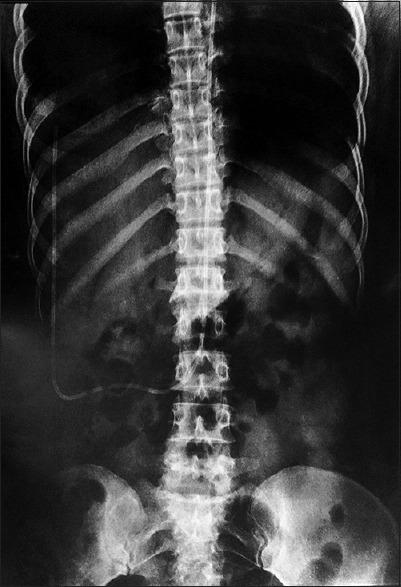

Ventriculoperitoneal Shunt (VPS) placement is one of the most commonly performed treatment modality in patient with hydrocephalus and infection is usually seen in such patients with shunt complication. Multiple shunt revision and its complications are related to various causes including mainly Coagulase negative Staphylococcus (CONS) infection. VPS obstruction occurring in proximal catheter is he most common cause of VPS malfunction. Here we present a case of Venticuloperitoneal shunt infection caused by CONS in a adult patient.

脑室腹腔分流术(VPS)置入是脑积水患者最常用的治疗方式之一,感染通常见于此类有分流并发症的患者。多次分流修复及其并发症与多种原因有关,主要包括凝固酶阴性葡萄球菌(CONS)感染。近端导管发生的VPS梗阻是VPS功能障碍最常见的原因。在此,我们报告一例成年患者因CONS引起的脑室腹腔分流感染病例。